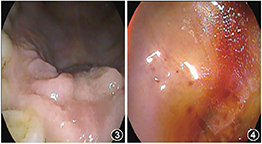

口腔检查:上颌前牙区肿胀隆起,硬腭正中前部局部隆起,触软,其对应的唇侧略隆起,触之软感(图3)。前鼻镜检查:鼻腔黏膜略充血,右侧鼻底部略隆起。鼻内镜示:鼻黏膜充血,右侧前部鼻底部略隆起,鼻道通畅,鼻咽部未见明显异常。诊断:鼻腭囊肿。

入院后完善术前常规检查后,于2020年7月10日在全身麻醉下行鼻内镜右侧鼻底开窗上颌骨肿物开窗术。术中先用彭氏电刀电凝右侧鼻底隆起处至黏膜发白,以减少术中出血,动力系统磨钻自隆起处前缘磨除鼻底骨质,咬骨钳及反咬钳咬除鼻底骨质扩大开窗口,进入囊腔,见大量咖啡色囊液流出,予以清理、止血,取部分囊壁送病理,彻底清除囊液,剩余上颌骨内囊壁予以保留。生理盐水反复冲洗术腔,彭氏电刀电凝开窗口边缘组织,膨胀海绵置于鼻底部压迫止血。手术顺利,术后予以抗感染等药物治疗,48 h抽出鼻腔膨胀海绵,检查见鼻底部开窗口开放较好,腔内黏膜水肿,术后病理结果回报:根尖囊肿。术后5 d患者康复出院。

术后1个月复诊,鼻内镜下见开窗边缘上皮化良好,囊腔内小许分泌物(图4)。